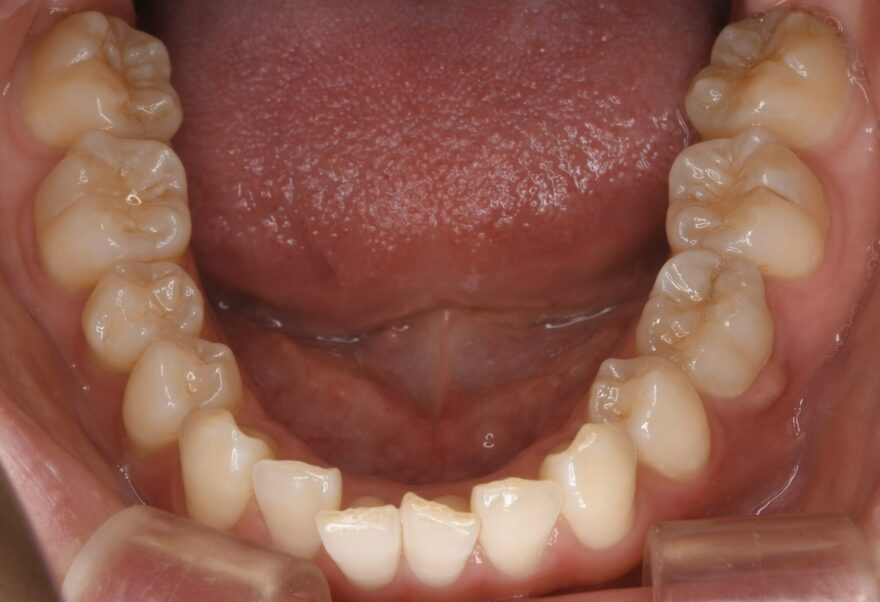

初診時の口腔内写真

前歯のガタガタが気になります。

治療後の口腔内写真

約2年の治療期間で、ここまで美しい歯並びになりました。

前歯も綺麗に並びました。

インプラントの上部構造は仮歯からセラミック歯へと交換しています。

下顎の前歯にはワイヤーによる保定装置を装着しました。